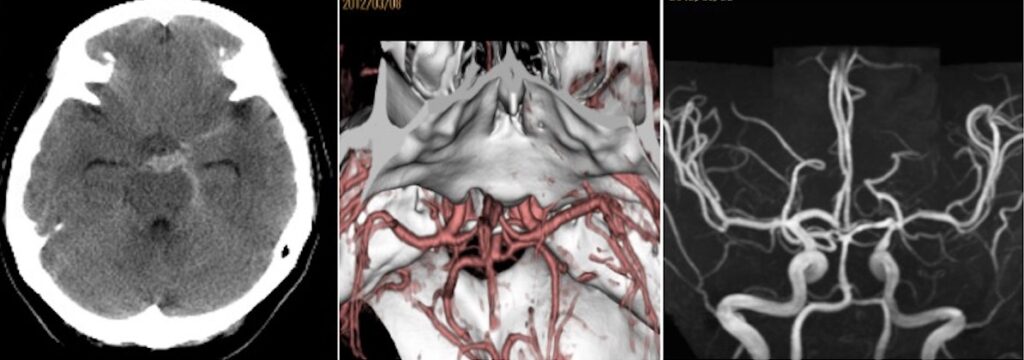

59歳女性の右中大脳動脈瘤を鍵穴クリッピングをしました。後遺症なしでした。 2025 12/12 脳動脈瘤・鍵穴 2025年12月12日13年前にくも膜下出血を起こしunknown SAHと診断され経過を見てきた患者さんに動脈瘤が徐々に育ってきたケースです。鍵穴クリップで対処しました。ScreenshotScreenshotScreenshotScreenshotScreenshotScreenshotScreenshotScreenshot 脳動脈瘤・鍵穴 よかったらシェアしてね! URLをコピーしました! URLをコピーしました! 251024金 橋本信夫先生に久しぶりにお会いしました。 251029水 第84回日本脳神経外科総会(パシフィコ横浜)初日 この記事を書いた人 kikuta 関連記事 未破裂中大脳動脈瘤の鍵穴クリッピング術を行いました。後遺症を認めませんでした。 2026年4月27日 2026年2月 52歳女性 左内頸動脈-眼動脈分岐部動脈瘤クリッピング術を行いました。 2026年3月21日 56歳女性 内頸動脈眼動脈分岐部動脈瘤クリッピング術をしました。軽度視野欠損が出ましたが無事退院されました。 2026年2月19日 63歳男性、右内頸動脈瘤開頭クリッピング術 2026年1月6日 58歳男性 中大脳動脈瘤を鍵穴クリップしました。合併症なく退院されました。 2025年12月17日 44歳女性 SAH PICA遠位部動脈瘤クリッピングを指導しました。 2025年12月17日 2025年5月 68歳女性未破裂Acom 動脈瘤6.6mmのクリッピング術 2025年9月26日 前交通動脈瘤をクリッピングしました 2025年2月26日